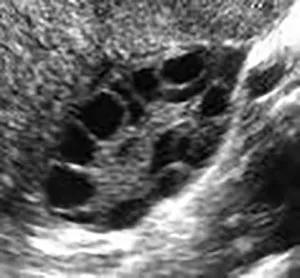

Polycystic Ovary Syndrome (PCOS) is a common reproductive endocrine disorder characterized by ovulatory dysfunction, excess androgen hormone levels, and polycystic appearing ovaries on ultrasound.

✔ Pelvic Ultrasound: Checks for multiple small ovarian follicles (often called a “string of pearls” appearance).